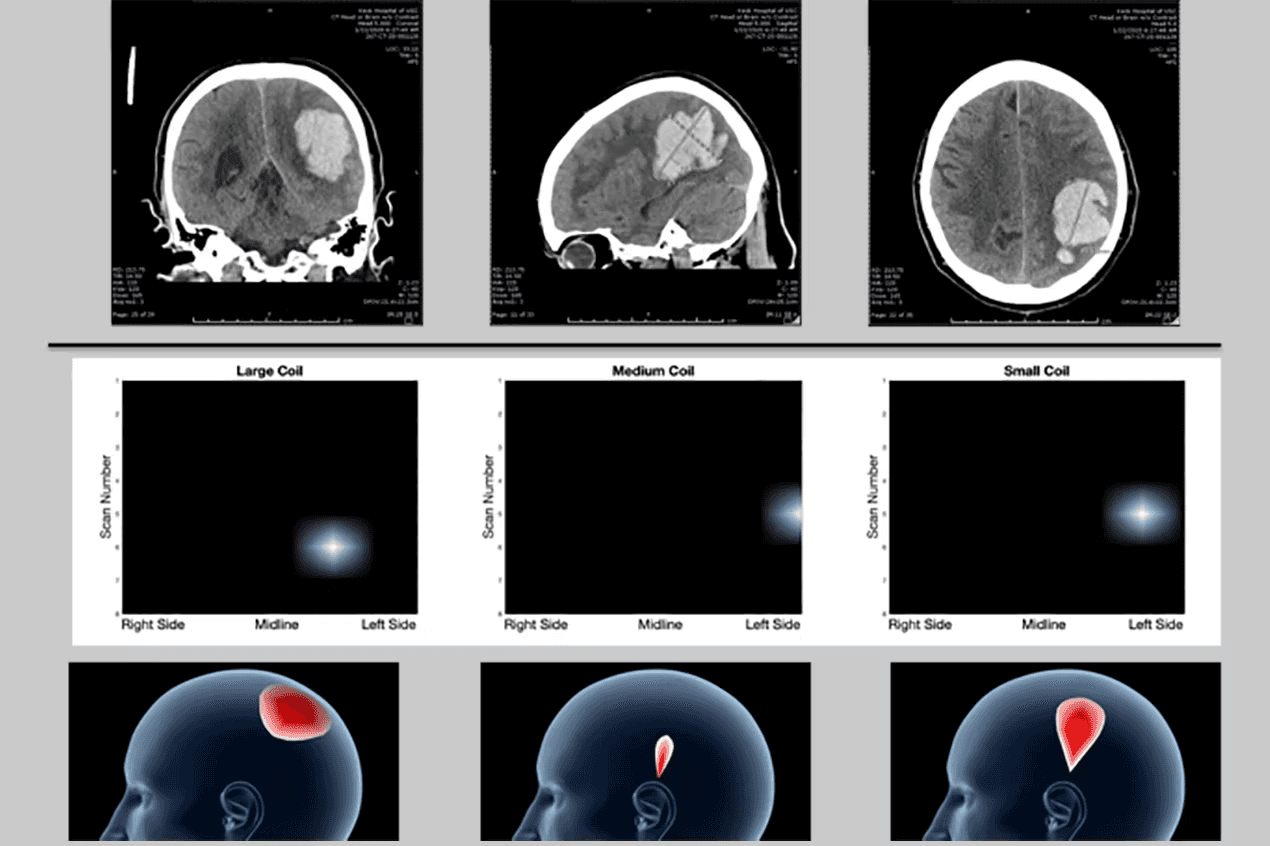

Recently, the technology underlying StrokeDx that uses eddy current damping techniques received a five-year $2.45M NIH R01 grant to further refine the device, test its ability to detect the depth and breadth of brain hemorrhage in patients, and develop algorithms to quickly and accurately classify brain lesions, as compared to CT and MRI scans.

The new device works as a rapid, portable, non-invasive, and affordable alternative to CT for stroke triage, with early studies showing a diagnostic time between 1 and 2.5 minutes for stroke sub-typing and imaging.